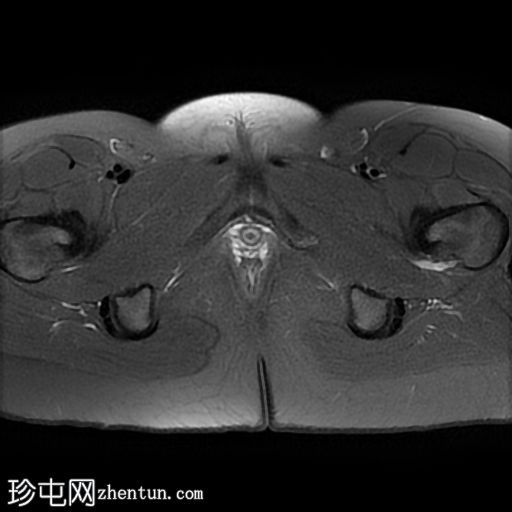

轴向T1

脂肪饱和度

子宫体相对较小,发育良好。宫颈发育不全。

阴道整体不显影,远端可见一层细小的纤维组织,在轴向和矢状面T2加权序列上最为明显。

随后,子宫内膜和宫颈腔扩张,出现混合液体/血液降解信号(积血)。它诱发中至高T1信号,伴有依赖性低信号碎片,无病理性强化。